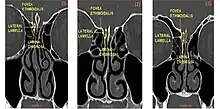

From left to right, Keros type I, II, and III.

The Keros classification is a method of classifying the depth of the olfactory fossa.

The depth of the olfactory fossa is determined by the height of the lateral lamella of the cribriform plate. Keros in 1962, classified the depth into three categories.[3]

• type 1: has a depth of 1–3 mm (26.3% of population)

• type 2: has a depth of 4–7 mm (73.3% of population)

• type 3: has a depth of 8–16 mm (0.5% of population)

• type 4: has asymmetric depths (described by Stammberger)